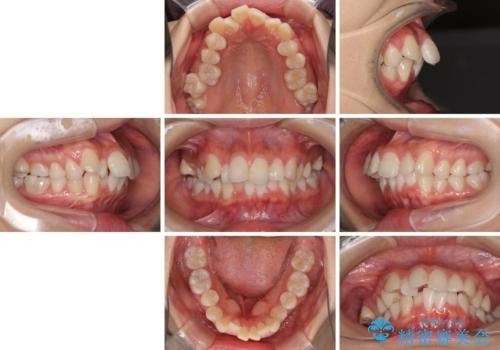

- 出っ歯とデコボコを気にして来院された患者様です。

口元の突出感を改善するため、上下左右第一小臼歯4本の抜歯を行い、ワイヤー装置による矯正治療を行うこととしました。

治療前の上下正中はずれていましたが、骨格的な上下左右差はあまり認められなかったため、正中を揃えて治療を終えることができました。

1年半ほどで治療を終えることができるとは我々も想像しておらず、患者様には大変満足していただきました。